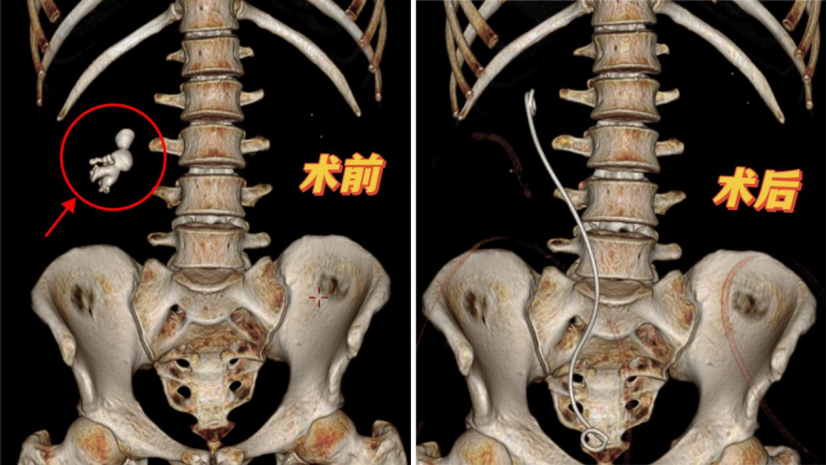

CT结果让所有人震惊!那颗被遗忘的小石头,已经在他右肾“发展壮大”成一个填满肾中下盏的“结石筑城堡”——医学上称为“铸型结石”,形态复杂就像珊瑚,已经把肾堵出了肾积水......

于是,泌尿外科专家团队最后决定为他量身定制一场“双镜合璧”的碎石手术——经皮肾镜联合肾盂软镜同期碎石手术。术中,许教授主刀,先在李明腰部开一个手指粗细的微创通道,将经皮肾镜(黄色箭头)伸入肾脏清理大块结石,配合肾盂软镜(蓝色虚线箭头)可弯曲的“身段”,钻入各个隐蔽肾盏,利用“碎石航母”配备的气压弹道、超声负压和激光把隐藏在深处的结石逐一击碎、取出。

专家团队默契配合,全程仅用一个微创通道,创伤小、出血少。一个半小时,李明肾脏里的“石头堡垒”被彻底清空,“战斗”顺利收官。